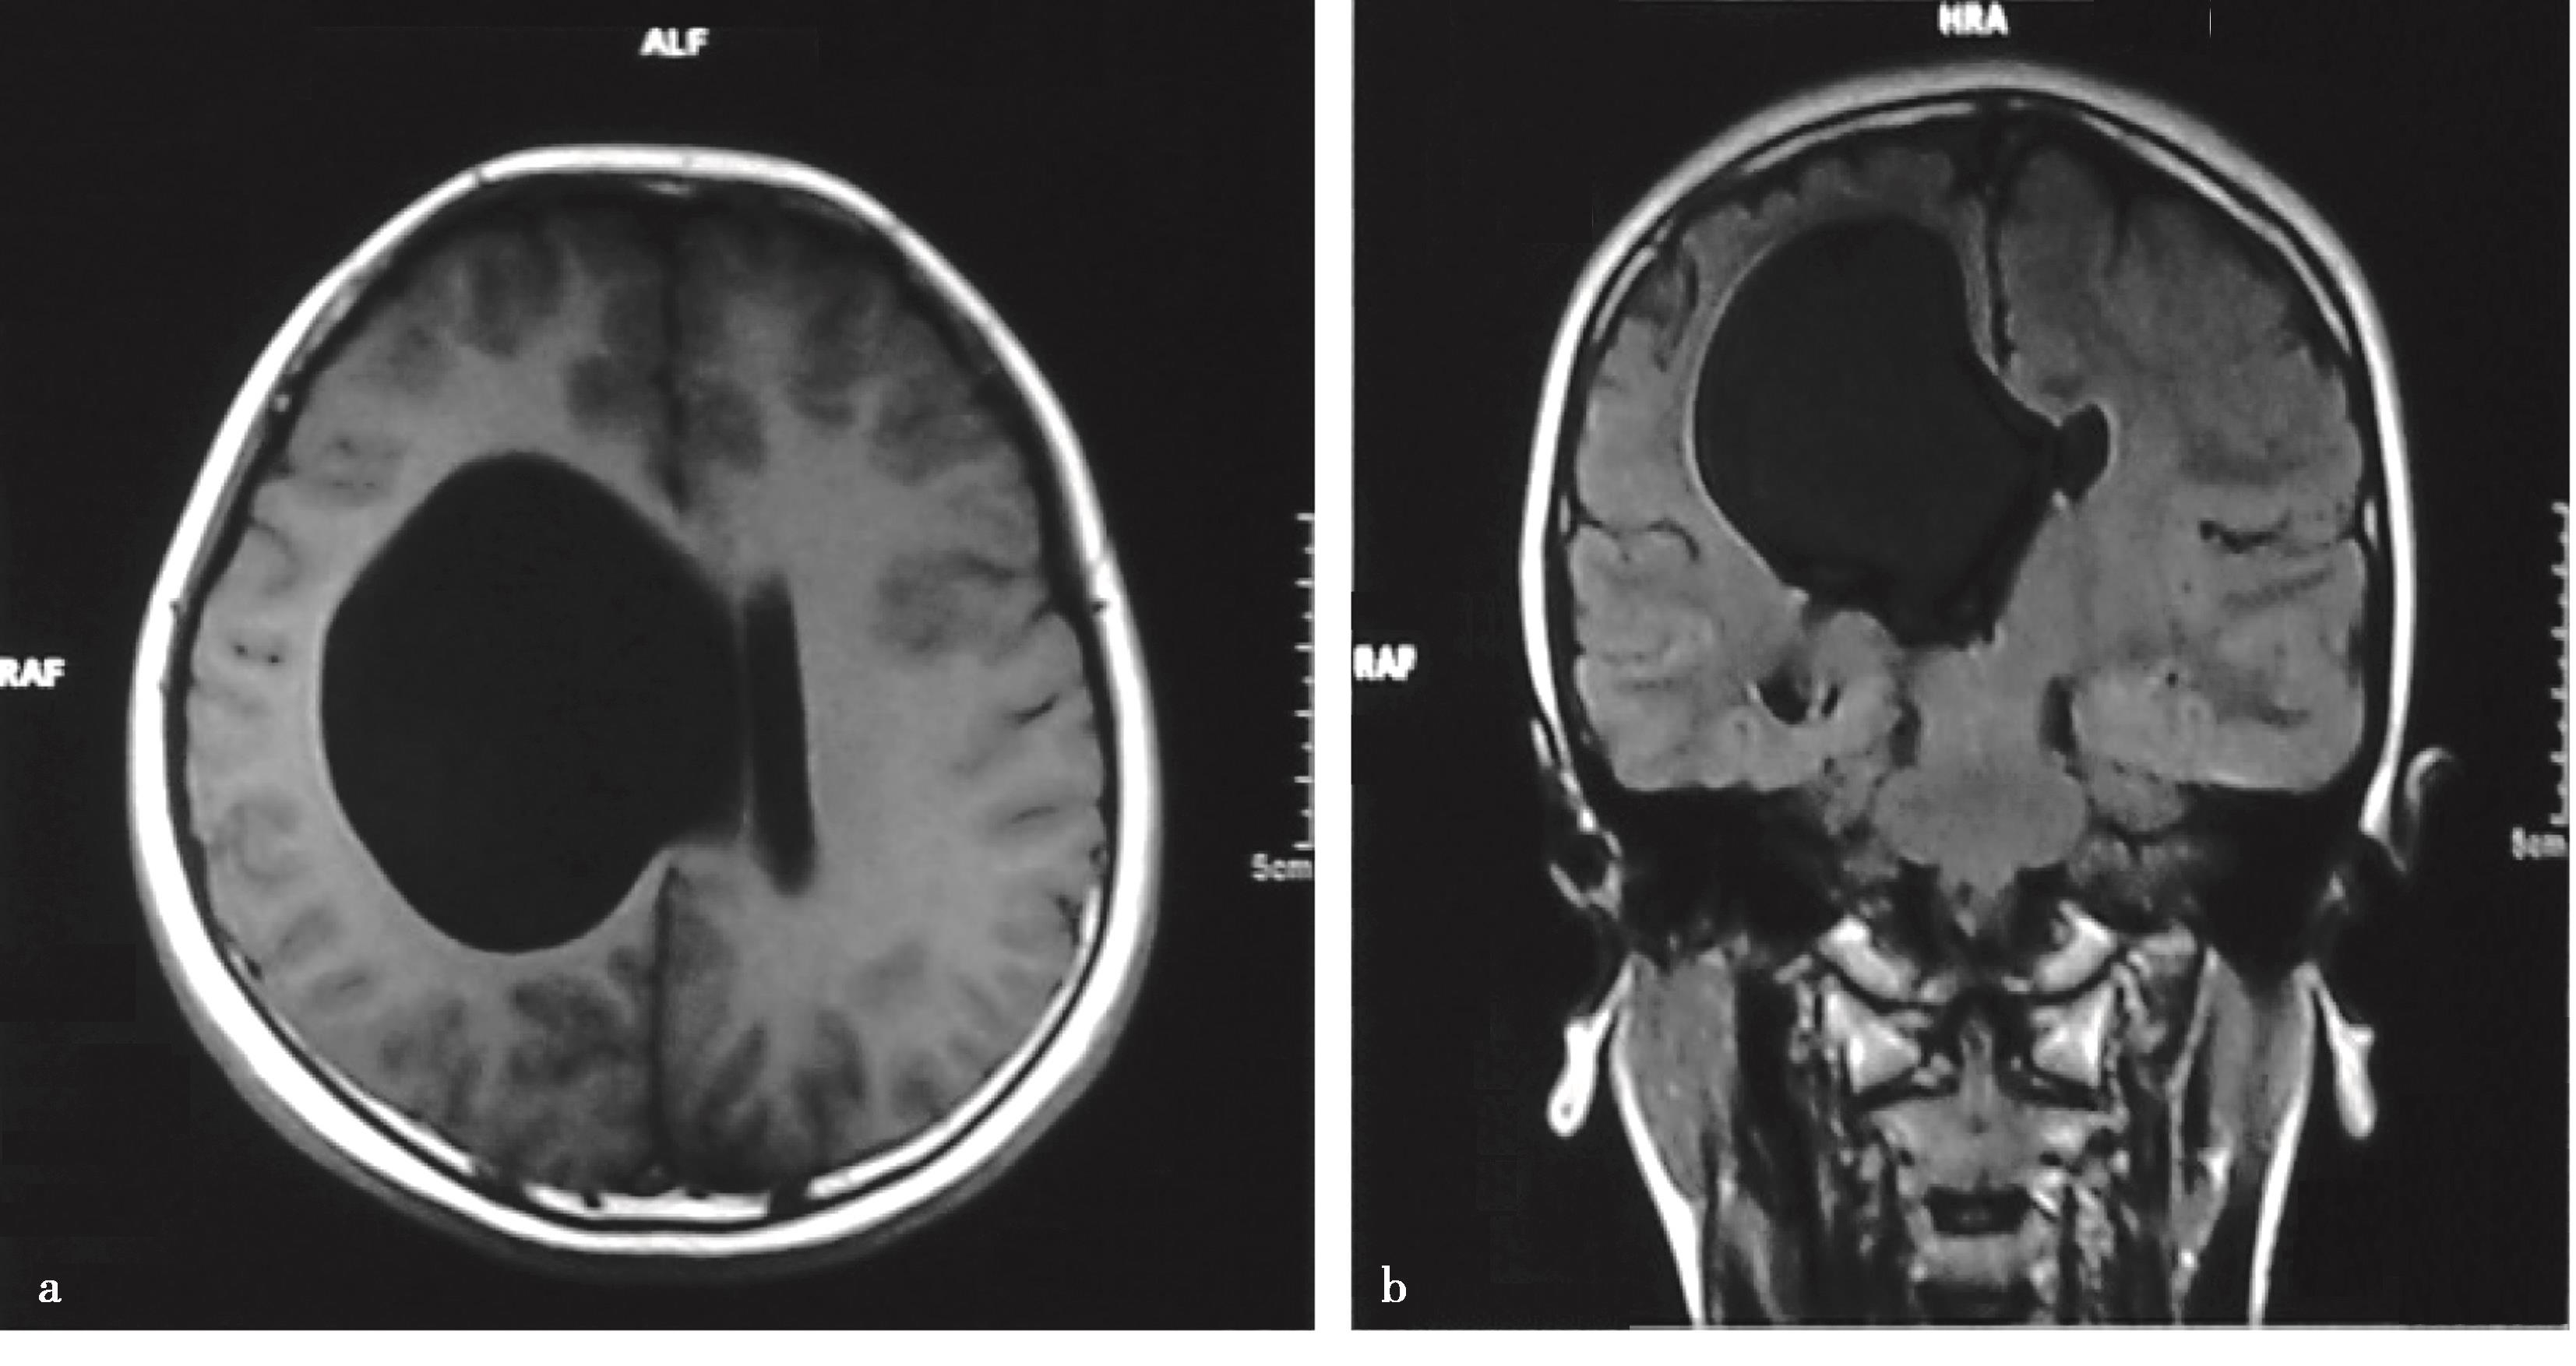

2.单侧或双侧室间孔狭窄或闭塞所致一侧或双侧侧脑室积水,采用内镜下室间孔成形术进行治疗(图3-1-2-1)。

图3-1-2-1 室间孔狭窄的影像学表现

a.右侧室间孔狭窄,头颅MRI轴位;b.右侧室间孔狭窄,头颅MRI冠状位;c.左侧室间孔狭窄,头颅MRI轴位;d.双侧室间孔狭窄,头颅MRI冠状位;e.内镜下可见左侧室间孔闭塞、右侧室间孔狭窄;f.内镜下可见左侧室间孔闭塞;g.内镜下可见右侧室间孔闭塞;h.室间孔球囊成形;i.经球囊成形后的室间孔